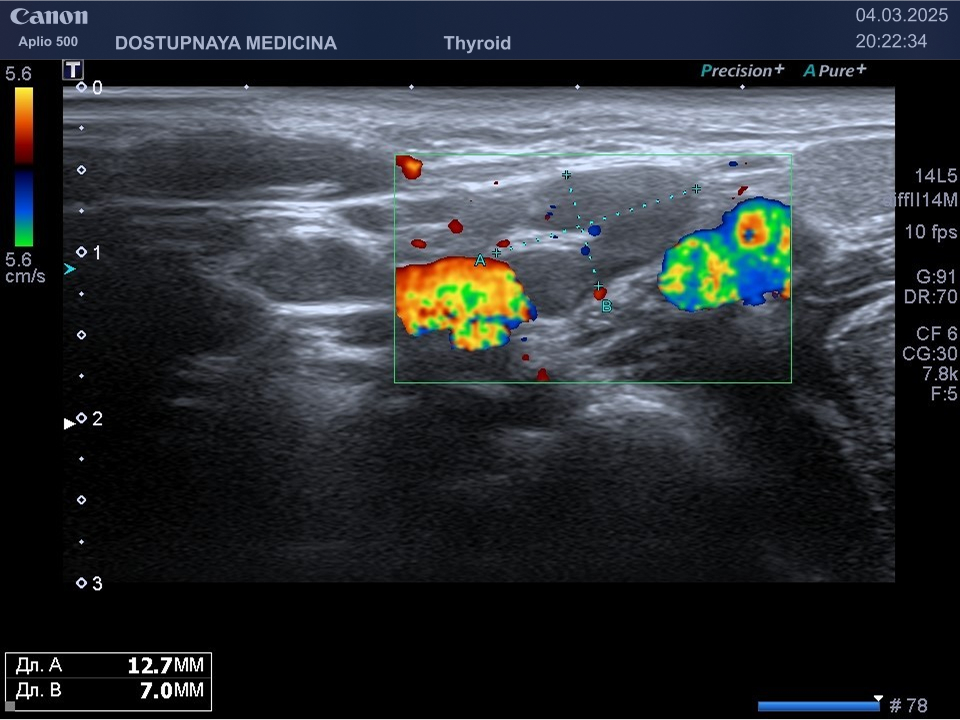

При ультразвуковом исследовании липосаркома чаще всего выглядит, как гипоэхогенное образование неправильной овальной формы, обычно с более пониженной эхогенностью (темнее) по сравнению с окружающей её подкожной жировой клетчаткой, с усиленным кровотоком в режиме ЦДК. В описании заключения важно так же отметить прилежит ли близко опухоль к какому-либо кровеносному сосуду или нерву.

Видно, что кровоток в образовании значительно усилен.